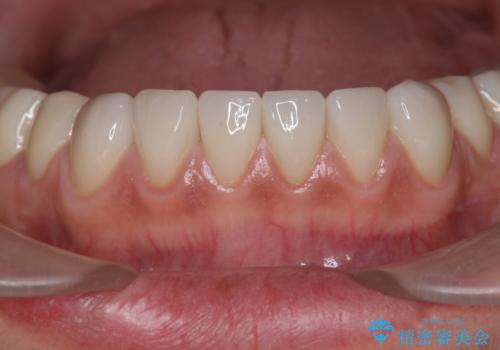

歯ぎしりですり減った 前歯の見た目を回復したい

- 歯ぎしり・嘔吐症により歯がすり減ってしまい、色調・見た目を改善したいと来院されました。

神経を温存したまま仮歯に置き換え、噛み合わせの安定を確認したのちに すり減りに強いジルコニアクラウンで最終的な仕上げを行います。